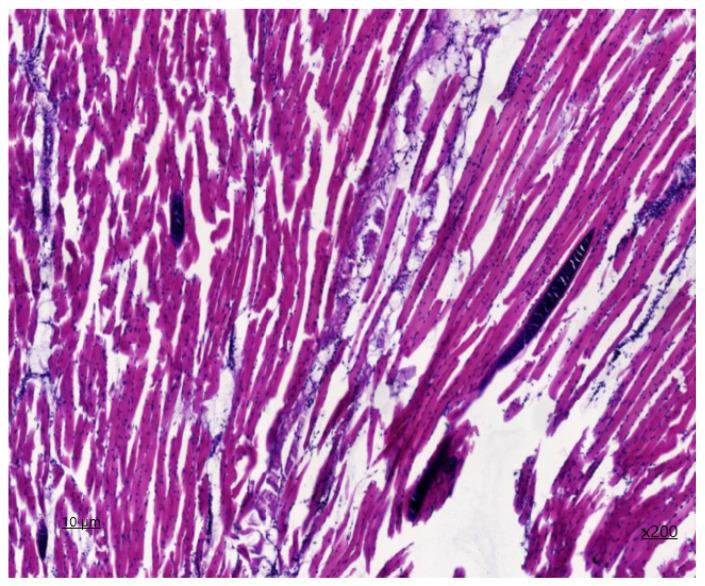

Histological examination revealed thick-walled cysts with internal septa and numerous bradyzoites, and mononuclear inflammatory cells with pericyst infiltrates. Microcyst samples were amplified by polymerase chain reaction. Molecular genetic analysis allowed for the identification of 18 sarcocysts. Phylogenetic analysis of isolates revealed three separate clades of and two separate clades of . Comparison and phylogenetic analysis revealed a very close relationship between the identified species and other equine DNA sequences from China and Japan. Based on the results obtained, the epizootic situation and the parasitic level of sarcocystosis contamination of horses in the northern Kazakhstan were determined.

组织学检查发现有带内部隔膜的厚壁囊肿和大量缓殖子,以及囊肿周围浸润的单核炎性细胞。微囊肿样本通过聚合酶链反应进行扩增。分子遗传学分析鉴定出18个肉孢子虫囊。对分离株的系统发育分析揭示了三个独立的 分支和两个独立的 分支。比较和系统发育分析表明,鉴定出的 物种与来自中国和日本的其他马属 DNA序列之间存在非常密切的关系。根据获得的结果,确定了哈萨克斯坦北部马的肉孢子虫病流行情况和寄生虫污染水平。